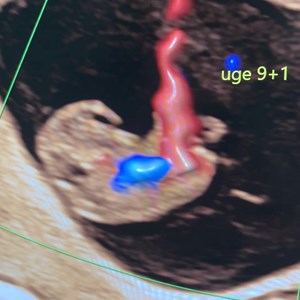

Den livsændrende oplevelse 💖 Det her billede viser for de fleste bare en mørk plet. Men ...